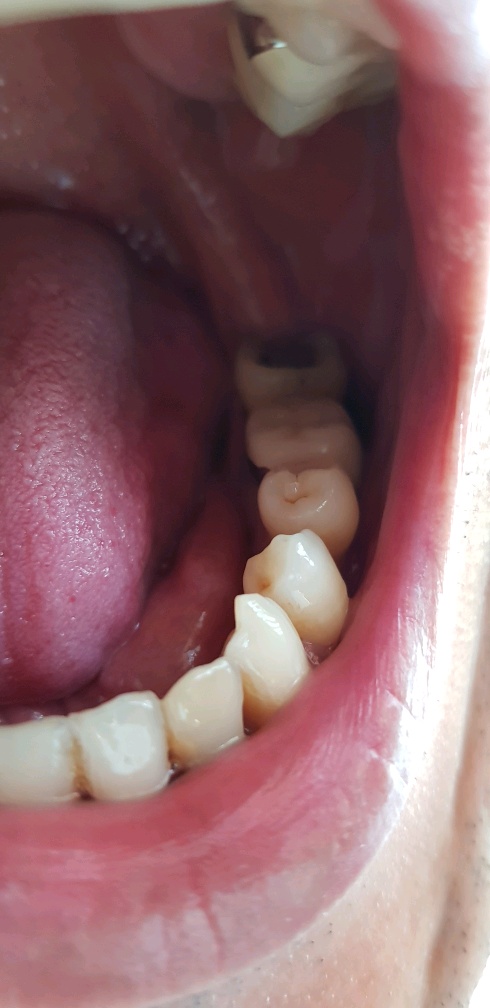

그렇게 뽑고, 긁어내고(제일 병맛같은 부분이 염증 긁어낼때임) 전동드릴로?? 단계별로 구멍 넓혀주고..

그렇게 30분 정도가 흐른 후 잘 박혔는지 엑스레이 찍고 후덜덜 한 상태로 드디어 끝났다...

잘심어진 건지는 모르겠으나.. 그냥 내가 겉보기엔 다행히도 잘 된거 같다..

근데 바로 앞의 치아뿌리가 왜저리 올라와 있는건지...;;

조만간에 저것도 해야된다고 하는거 아닌가 모르겠다 쩝..